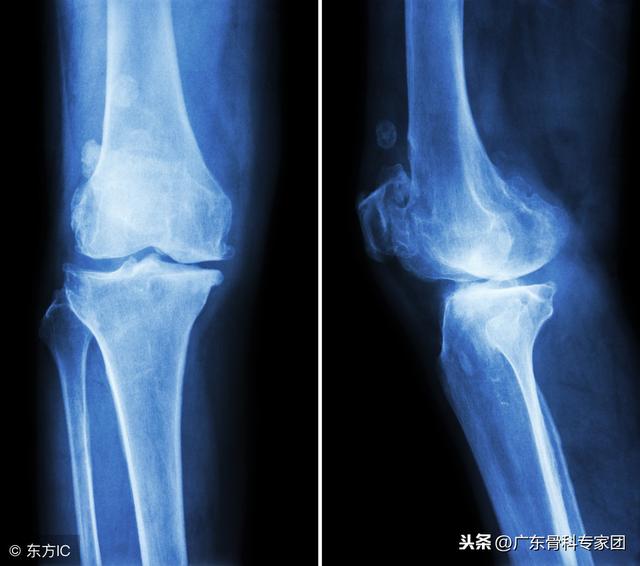

关节上有骨刺,需要除掉吗?

骨质增生的本质是人体骨骼的一种“衰老”现象,是一种正常的生理现象。随着年龄的增长,人的脊柱和关节周围的肌肉、韧带等组织会发生退行性改变,使脊柱和关节的平衡遭到破坏,出现脊柱和关节的不稳定。

机体为了适应这些变化,恢复新的平衡状态,就会通过骨质增生的方式增加骨骼的表面积,减少骨骼单位面积上的压力,使脊柱或关节更加稳定??梢运?,骨质增生现象是机体的一种自我保护机制,是机体的一种本能。

只是有时骨质增生造成了疼痛、肿胀、肢体功能障碍等症状,使人感到不舒服时,老年人才把骨质增生作为疾病来看待。所以,我们可以把膝关节的骨刺打磨掉,让关节变得光滑,减少其对膝关节半月板软骨的磨损,减轻膝关节疼痛不适的症状,比如说在膝关节镜下做微创清理术,也可以有很好的效果。